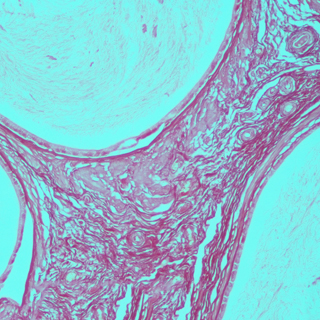

正常情況下,除脂肪細胞外其他細胞內-般不見或僅見少量脂滴。在病理狀態下如這些細胞中出現脂滴或脂滴明顯增多,特別是在心、肝.腎等實質器官發生脂肪變性時,胞漿內出現大小不一的空泡, 這時常需鑒別空泡性質,用脂肪染色來區分是脂肪變性還是水樣變性或糖原貯留。在動脈粥樣硬化時,內皮細胞下的脂質沉著,用脂肪染色能將脂質清晰地顯示出來。由脂肪組織病變所弓|起的脂肪栓塞可用脂肪染色顯示栓子內的脂質,從而確診脂肪栓塞。用于腫瘤組織的鑒別診斷,由脂肪組織所發生的腫瘤在與其他組織來源的腫瘤相區分時,可以借助脂肪染色,脂肪組織所發生的腫瘤,脂肪染色為陽性。并可根據所顯示的細胞形態特點與類似腫瘤進行鑒別,腎透明細胞癌與腎上腺瘤,卵巢纖維瘤與卵泡膜細胞瘤。皮脂腺瘤與鱗狀細胞癌的鑒別診斷有意義。